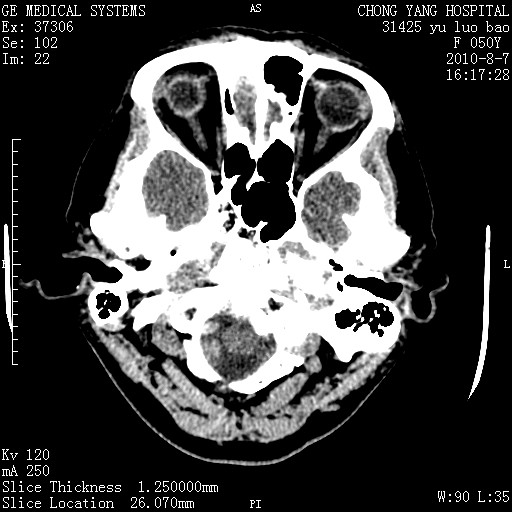

标题: CT28285:听力下降一年,头昏。

右侧桥小脑角去等密度占位,右侧内听道扩大、骨质吸收,考虑:右侧听神经瘤,建议增强检查。

右侧内听道扩大、骨质吸收,中脑受压左移,考虑:右侧听神经瘤,建议增强检查。支持!

右侧桥小脑角区等密度占位,内耳道扩大,听神经瘤